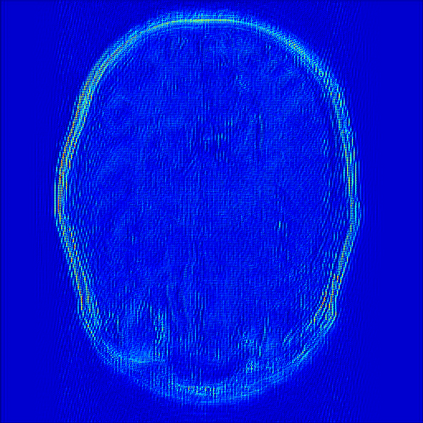

Reconstructing magnetic resonance (MR) images from undersampled data is a challenging problem due to various artifacts introduced by the under-sampling operation. Recent deep learning-based methods for MR image reconstruction usually leverage a generic auto-encoder architecture which captures low-level features at the initial layers and high?level features at the deeper layers. Such networks focus much on global features which may not be optimal to reconstruct the fully-sampled image. In this paper, we propose an Over-and-Under Complete Convolu?tional Recurrent Neural Network (OUCR), which consists of an overcomplete and an undercomplete Convolutional Recurrent Neural Network(CRNN). The overcomplete branch gives special attention in learning local structures by restraining the receptive field of the network. Combining it with the undercomplete branch leads to a network which focuses more on low-level features without losing out on the global structures. Extensive experiments on two datasets demonstrate that the proposed method achieves significant improvements over the compressed sensing and popular deep learning-based methods with less number of trainable parameters. Our code is available at https://github.com/guopengf/OUCR.